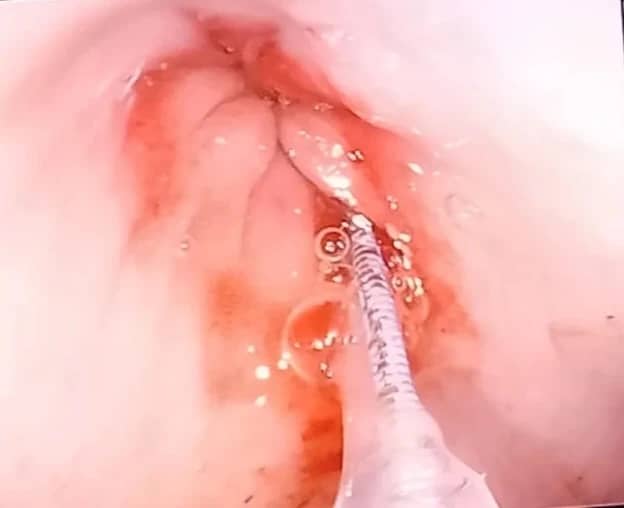

- Срыгивание (регургитация) — это пассивный процесс. Пища выходит без усилий, часто неожиданно для самого питомца, через несколько минут после еды. Она выглядит как непереваренная «колбаска» в слизистой оболочке, потому что не успела попасть в желудок